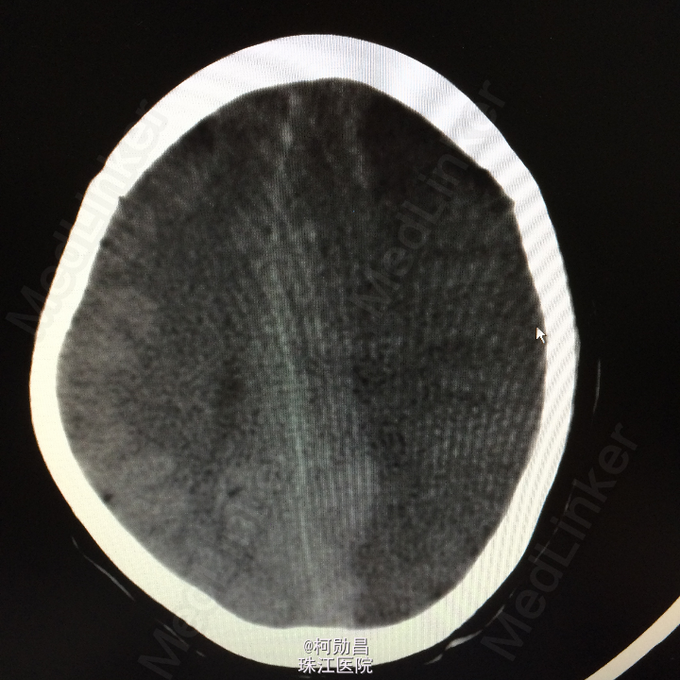

查体:神志呈昏睡状态,言语不能,精神差,双侧瞳孔不等大,左侧3mm,对光反射消失;右侧瞳孔2,mm,对光反射灵敏,右侧肢体肌力0级,左侧肢体肌力5级,右侧肢体肌张力减低,余未见异常。 辅助检查:左侧大脑半球累计岛叶、基底节区(以颞顶叶为主)大片状低密度影,考虑脑梗塞;中线结构明显右移。